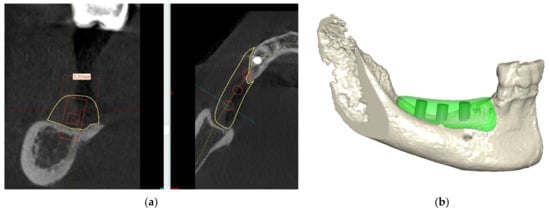

Due to the severe atrophy in the posterior mandible, different treatment options were discussed with the patient, and after agreement, informed consent was signed, including all the different potential risks and complications. The patient was extensively informed about vertical bone augmentation utilizing an allograft Customized Bone block (Puros® Allograft Customized Bone Block, Zimmer-Biomet Dental, Palm Beach Gardens, FL, USA) to reconstruct the lost hard tissue volume in the vertical and horizontal dimensions. Based on the CBCT evaluation and the implant position, the exact size of the block was determined (Figure 4a,b).

Figure 4.

(a,b) Bone block design.